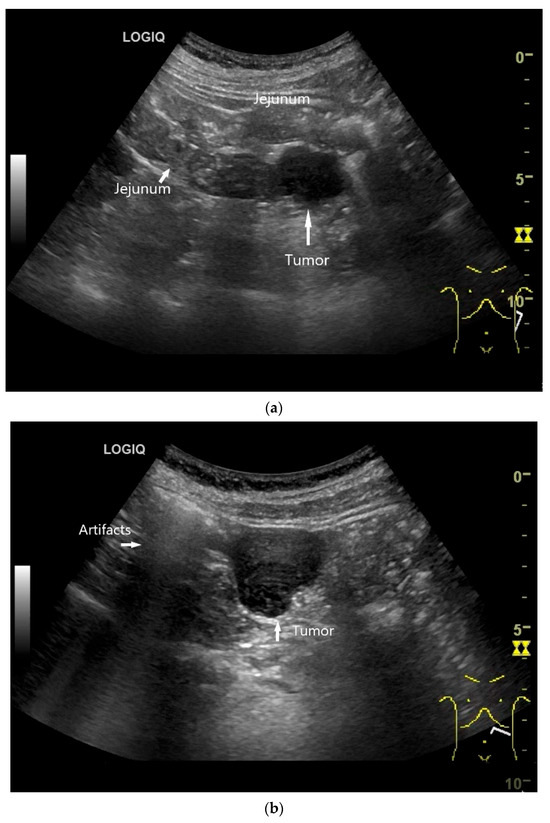

Figure 10.

Diffuse large B-cell lymphoma (DLBCL). In the right mid-lower abdomen, a large, smoothly circumscribed mass is present around the ileum (“pseudo kidney sign” (a)). Using a high-resolution linear transducer, the mass appears smoothly circumscribed and almost anechoic (b). The ileum runs centrally, and the echogenic wall is clearly defined (c). This wall does not merge into the mass. Since the mass is almost anechoic, it is also difficult in different transducer positions to distinguish whether it is a liquid lesion or a solid mass (b,c). CEUS with 2.4 mL SonoVue (9 MHz linear transducer) shows homogeneous arterial enhancement (d), but the intensity decreases with time in the venous phase (e). The ileal wall enhancement centrally within the mass is more intense than that of the tumor (d,e).